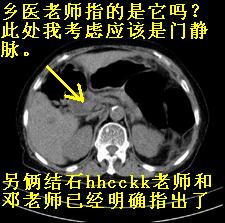

患者,女,75岁。腹痛,体黄5日,膝胸位时腹痛缓解。肝功能明日出来。彩超提示胆总管占位,未见血流信号。心电图提示s-t段改变。患者体质较弱,未能增强。

胆总管上段,腔内有软组织密度影 ,ct值36-44hu。大家看有没有胆管癌的可能。

2楼所说胰腺内钙化不像,象脾脏血管的钙化

典型胆总管多发结石;增强扫描前后ct值是否发生改变是鉴别结石与占位的依据。